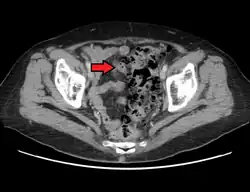

- Contrast CT is the investigation of choice in acute episodes of diverticulitis and where complications exist.

Infection of a diverticulum can result in diverticulitis. A 2013 study[11] found that it happens only about 4% of the time. That contradicts the prevailing thinking that 10% to 25% of people with diverticulosis go on to develop diverticulitis. Tears in the colon leading to bleeding or perforations may occur; intestinal obstruction may occur (constipation or diarrhea does not rule this possibility out); and peritonitis, abscess formation, retroperitoneal fibrosis, sepsis, and fistula formation are also possible occurrences. Rarely, an enterolith may form. Infection of a diverticulum often occurs as a result of stool collecting in a diverticulum.

Diverticulitis is defined as diverticular disease with signs and symptoms of diverticular inflammation. Clinical features of acute diverticulitis include constant abdominal pain, localized abdominal tenderness in the left lower quadrant of the abdomen, nausea, vomiting, constipation or diarrhea, fever and leukocytosis.[12]